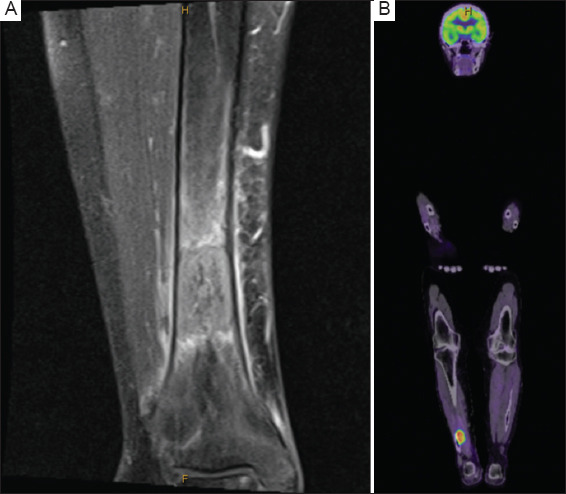

背景:膀胱癌(BCa)经常转移到骨骼,通常影响脊柱和骨盆。病例介绍:本文报告一例罕见的广泛胫骨远端转移病例,患者为84岁女性,患有侵袭性高级别尿路上皮癌,踝关节疼痛迅速进展,活动能力降低。影像学和活检证实转移性尿路上皮癌在胫骨,这是管理手术固定和姑息性放疗。虽然BCa的骨转移通常会影响其他部位,但临床医生应考虑非典型部位,如胫骨,患者有不明原因的骨痛。结论:早期诊断和干预对改善患者预后和生活质量至关重要。

Case presentation: Presented here is a case of rare extensive distal tibia metastasis in an 84-year-old female with invasive high-grade urothelial carcinoma, who suffered from rapidly progressive ankle pain and reduced mobility. Imaging and biopsy confirmed metastatic urothelial carcinoma in the tibia, which was managed with surgical fixation and palliative radiotherapy. Although bone metastases in BCa commonly affect other sites, clinicians should consider atypical locations like the tibia in patients with unexplained bone pain.